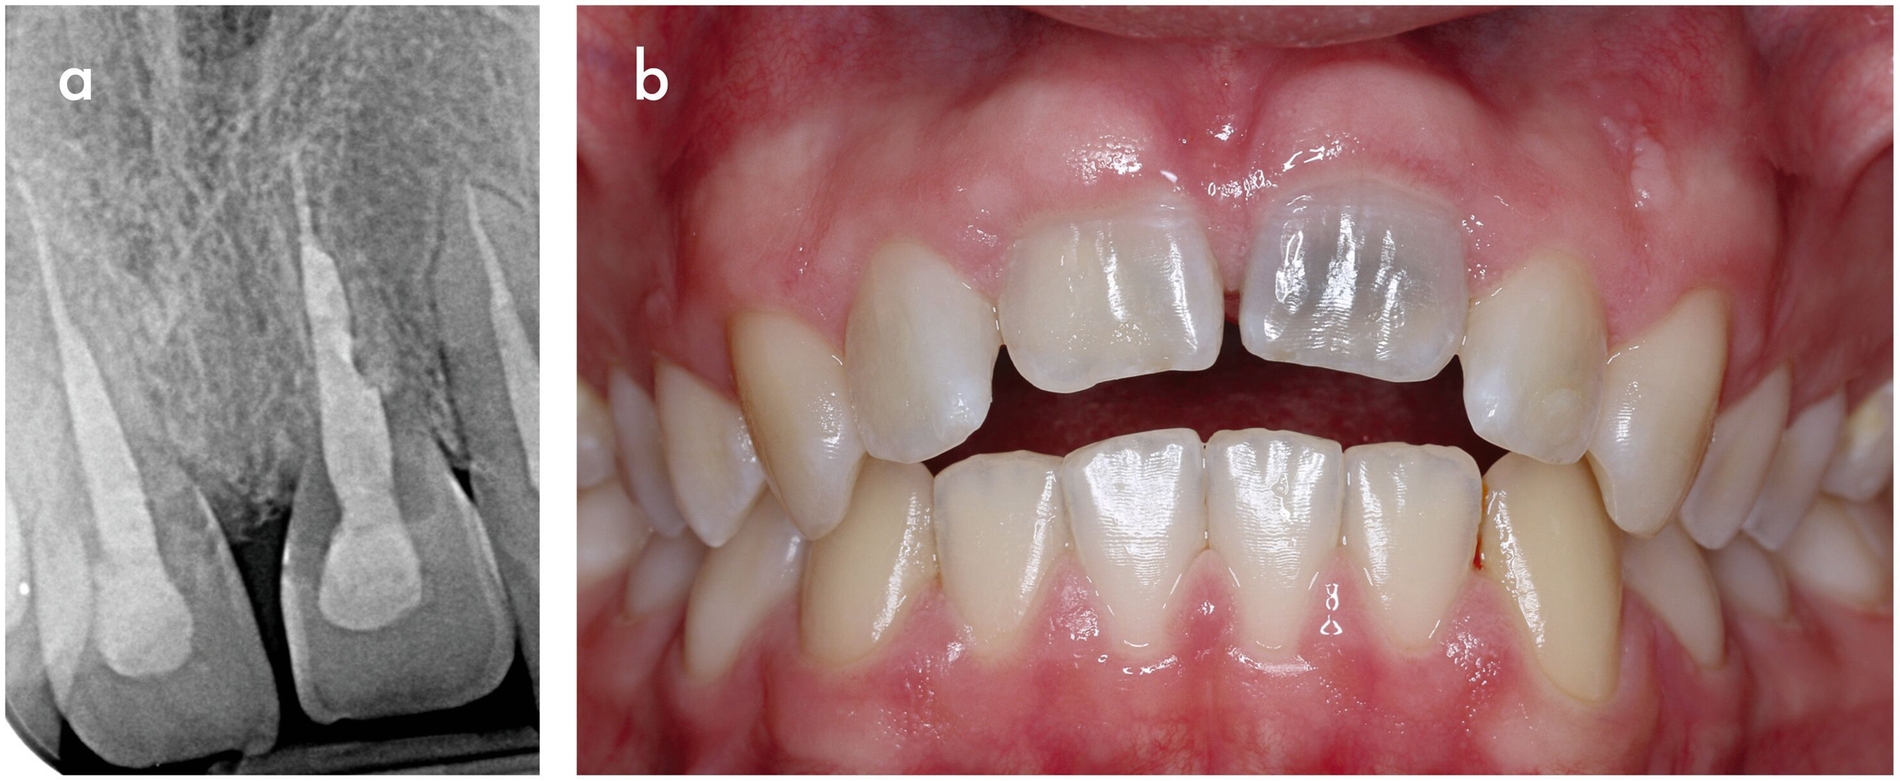

Klinisch handelt es sich häufig um Zufallsbefunde, die im Frühstadium asymptomatisch verlaufen. Bei der Untersuchung finden sich oft tastbare Defekte im Zahnhalsbereich, die mit leicht blutendem Granulationsgewebe gefüllt sind (Abbildung 7a). Mit zunehmender Größe können diese sich als rötliche Verfärbung der Zahnkrone darstellen, die als Pink-Spot-Läsionen bekannt sind (Abbildung 7b). Im Röntgenbild sind wolkige Aufhellungen im Bereich des Zahnhalses zu erkennen (Abbildungen 7c und 7d). Charakteristisch ist auch das intakte perikanaläre Dentin, das eine Schutzbarriere um den Wurzelkanal bildet und zusammen mit der vitalen Pulpa lange unversehrt bleibt [Patel et al., 2018; Patel et al., 2009].